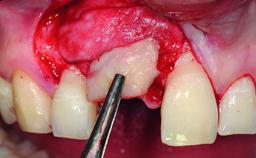

A healthy 28-year-old female patient presented for a consultation on treatment options to restore her upper right central incisor. At the clinical examination, the tooth responded to percussion and palpation. The gingiva was red and slightly swollen, with a mid-facial probing depth of 10 mm. The upper right lateral incisor showed no signs or symptoms, did not respond to exploration and percussion, and the vitality test was positive. The periapical radiograph revealed that tooth 11 had been endodontically treated, with no lesion evident at the apex. A small radiopaque calcified structure surrounded by a narrow radiolucent zone (3 × 3 mm) was present at the apex of tooth 12.

Bone Augmentation Horizontal|Simultaneous

Augmentation Materials Autogenous chips|Xenogenous|Membrane

Bone Volume Deficient horizontally, allowing simultaneous augumentation